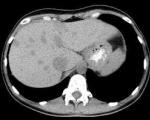

• КТ органов брюшной полости. Компьютерная томография с контрастированием - самая информативная. В зависимости от фазы усиления контраста пелиоз визуализируется как расширенные сосуды с интенсивным накоплением контраста или как диффузное увеличение интенсивности сигнала.